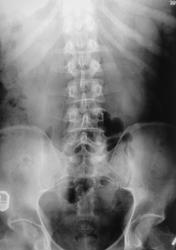

левой почки на уровне 11 12 рёбер определяются тени конкрементов размером до 5-7мм с неровными контурами. Видимо камни в левой почке в её ЧЛС.

После введения контраста.

Спасибо за исследование! Снимки отличные!А в левой лоханке-каменюка рентгеннегативная застряла (в виде дефекта наполнения)?

Naira, скорее, парапельвикальная киста.